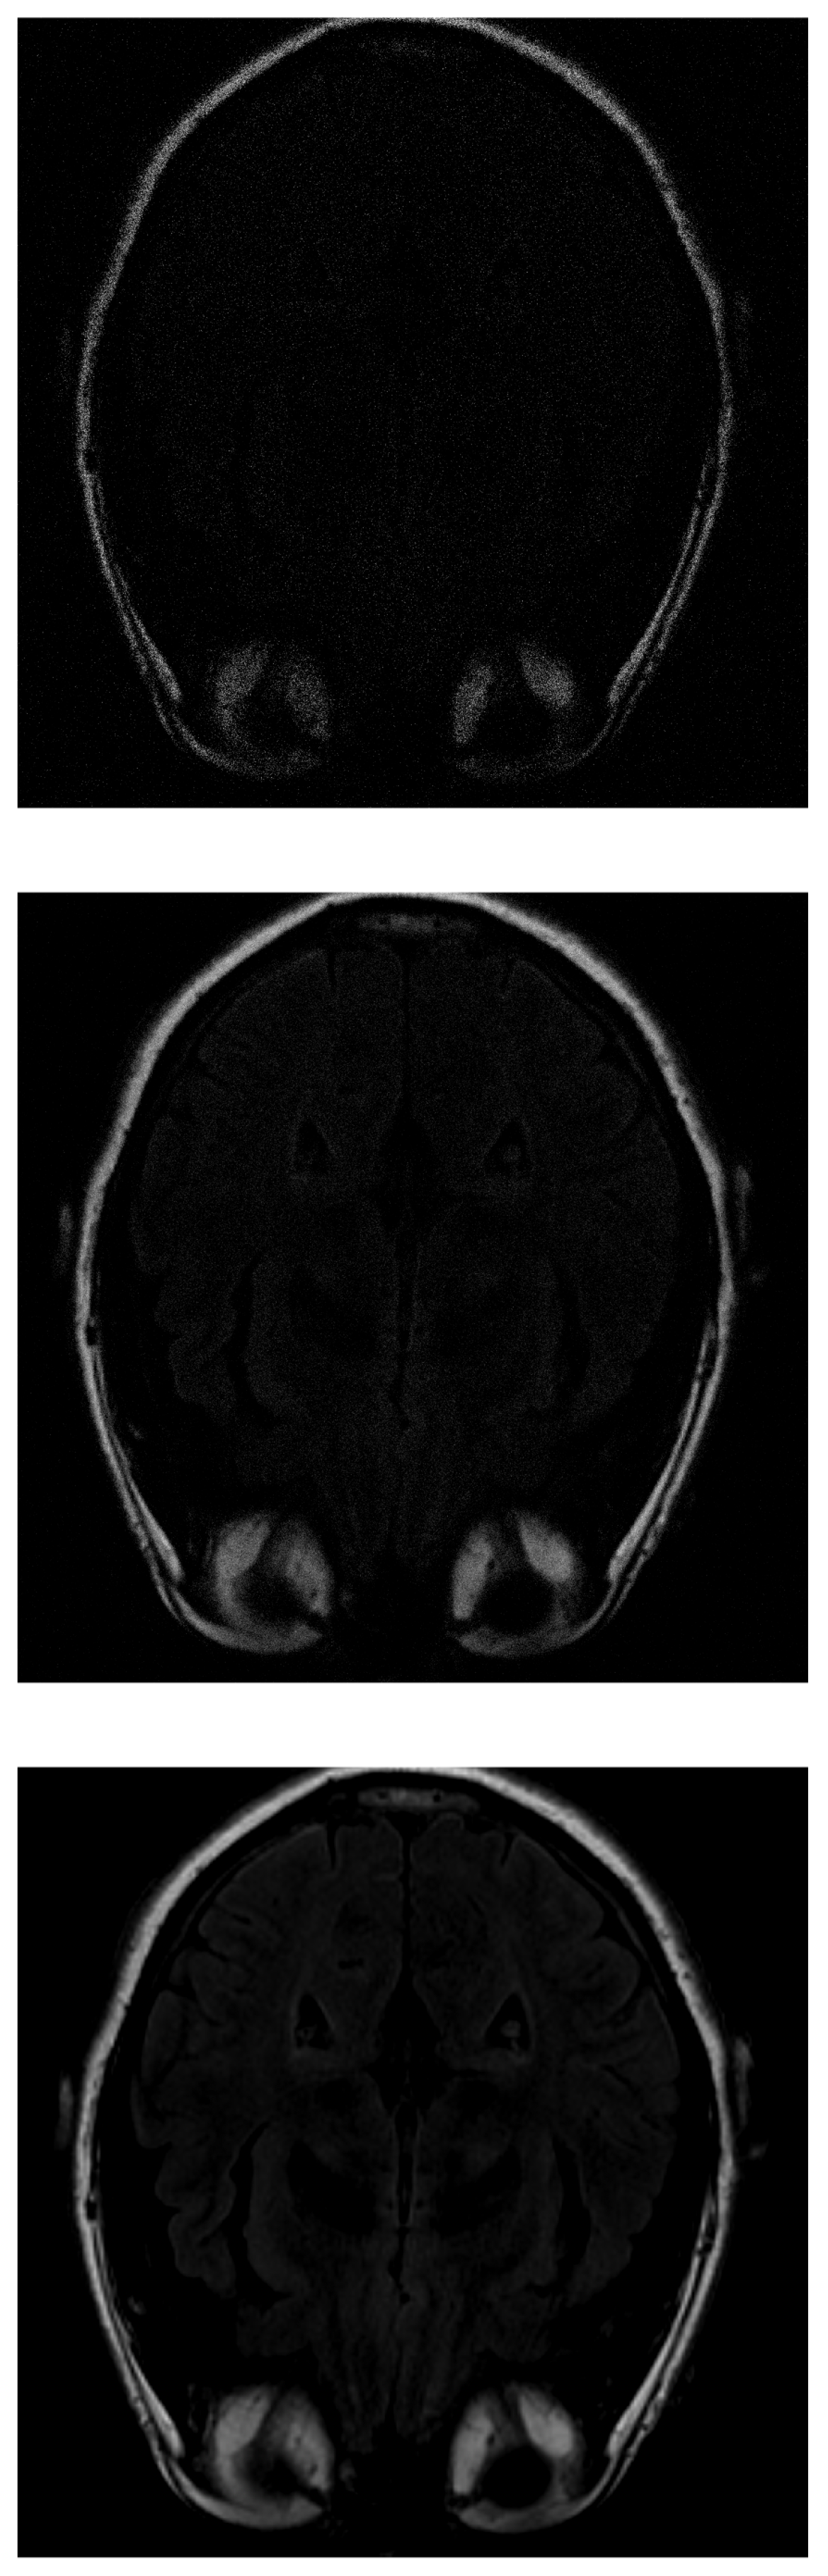

As in IRLS, the ISTA algorithm first detects the areas of highest intensity in the first measurements without distinguishing the white matter (Figure 6 top). If the number of input data is increased, the border resolution increases, but it is still difficult to differentiate the white matter (Figure 6 middile). Finally, the resolution increases until the shape of the fat is detected (Figure 6 bottom).

Figure 6.

Reconstruction of the image in Figure 3 using ISTA with (top), (middle) and (bottom) of taken measurements.